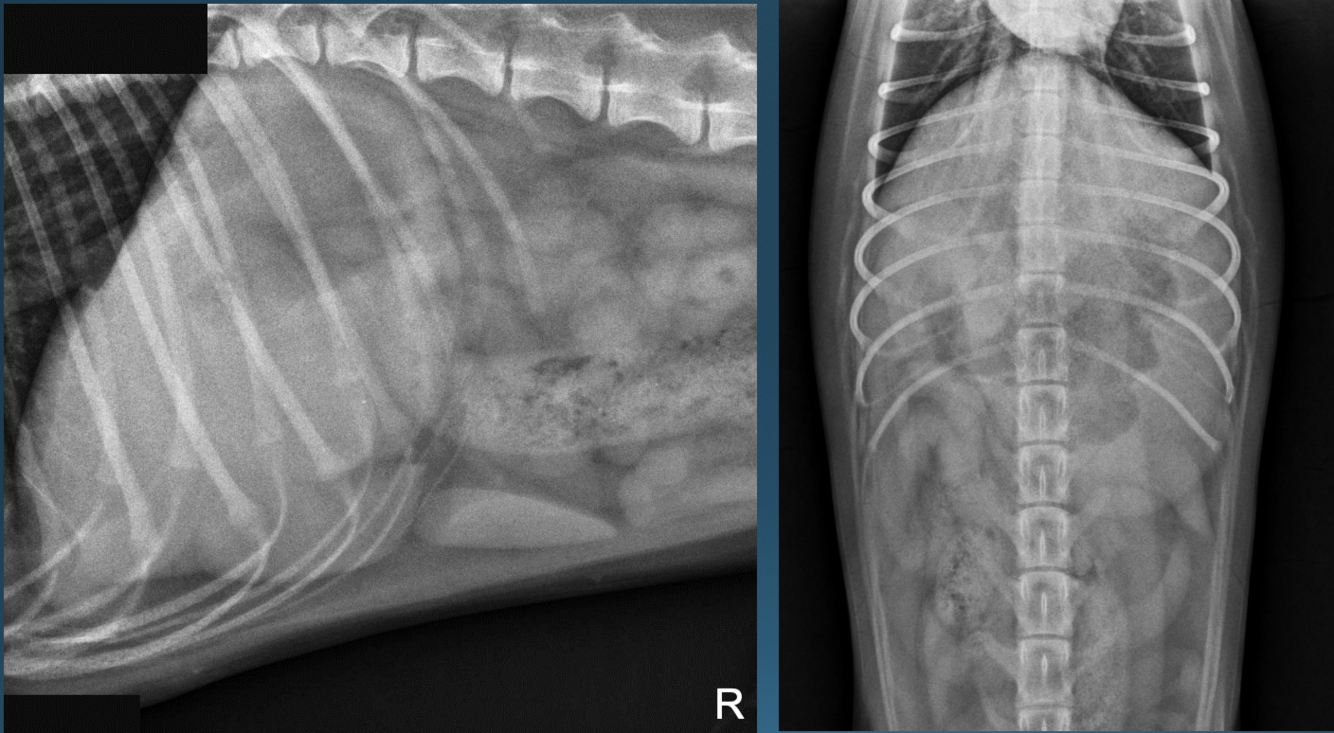

What is shown in these images?

A

canine acute gastric outflow obstruction:

-stomach slightly distended with fluid and gas

-hard to see stomach margins